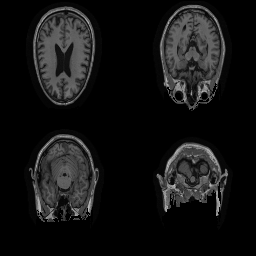

| Original | Renderings after de-identification | Original | MRI slices after de-identification | ||||||

| CP-GAN | FACE MASK | DEFACE | QUICKSHEAR | CP-GAN | FACE MASK | DEFACE | QUICKSHEAR | ||

Benchmark De-Identification Methods. We compare our result with three publicly available and widely-established methods for de-identification of MRI head scans, depicted in Figure 3. All methods have in common that they (1) are not deep-learning-driven, (2) require no additional training and (3), are used on a day-to-day basis in neuroscience and clinical research. All procedures were applied with default settings on images of resolution . The methods include QUICKSHEAR [Schimke et al.(2011)Schimke, Kuehler, and Hale], FACE MASK [Milchenko and Marcus(2013)], and DEFACE [Bischoff-Grethe et al.(2007)Bischoff-Grethe, Ozyurt, Busa, Quinn, Fennema-Notestine, Clark, Morris, Bondi, Jernigan, Dale, Brown, and Fischl]. Descriptions of the methods are provided in the Appendix. We also include MRI WATERSHED [Ségonne et al.(2004)Ségonne, Dale, Busa, Glessner, Salat, Hahn, and Fischl], a skull-stripping method that removes everything except the brain.